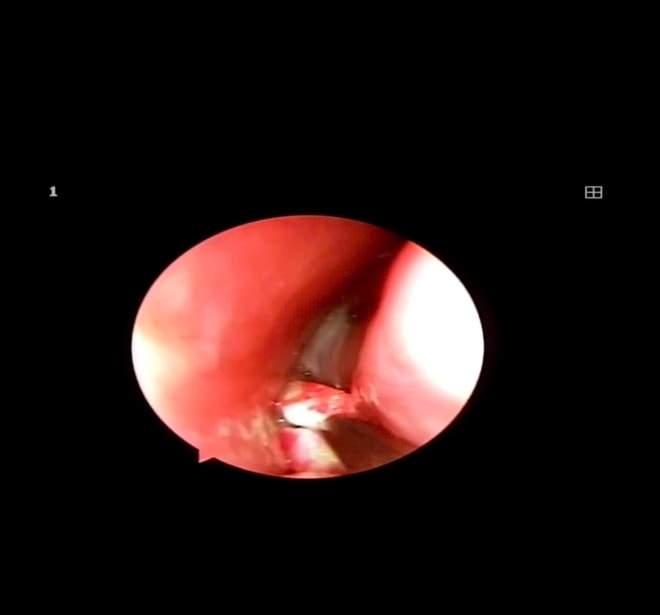

ThS.BSCKII Trịnh Thị Vân, người trực tiếp thăm khám cho biết: “Khi đến bệnh viện, trong hốc mũi trái của trẻ có rất nhiều dịch mủ, bé đau, quấy khóc nhiều. Sau khi làm sạch mũi và tiến hành soi kiểm tra, chúng tôi phát hiện một sợi dây chun nằm sâu trong hốc mũi – nguyên nhân chính gây viêm nặng cho các tổ chức xung quanh".

Ngay khi phát hiện dị vật, các bác sĩ Khoa Tai Mũi Họng đã tiến hành gây tê và nội soi lấy dị vật, thủ thuật được thực hiện nhanh chóng, an toàn và chính xác.

Dị vật là sợi dây chun được bác sĩ lấy ra thành công.